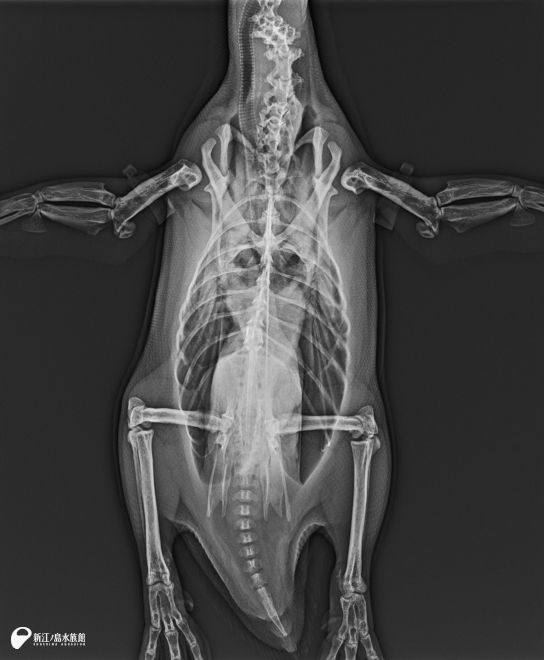

次は、X線診断装置(レントゲン)。

体にX線を照射し、骨や臓器を透過して放射線の濃淡を画像化することで、体内の状態を調べる装置です。骨の状態を容易に観察することができるので、骨折や関節炎、そして肺炎の診断に使用します。レントゲンは 2台の機械を持っています。

2025年 フンボルトペンギン「コメ」全身レントゲン。内臓の大きさの変化や膝や股関節の関節炎の進行具合などを観察し、この体勢以外に他 4方向から撮影します。15歳以上の高齢ペンギンは年に 2回、それ未満のペンギンたちは年に 1回の検査を実施しています。

2025年 パービャウ(淡水魚)のレントゲン。なぜパービャウのレントゲンを撮ったのか… この画像をじっくり見れば分かる人もいるかも。実はこの時、給餌に使う棒の針金を飲み込んでしまい、急遽レントゲンを実施しました。レントゲン写真にはしっかりと針金が写っています。幸い、口を開けたところで止まっていたのでピンセットで取り除き、無事に水槽に戻りました。